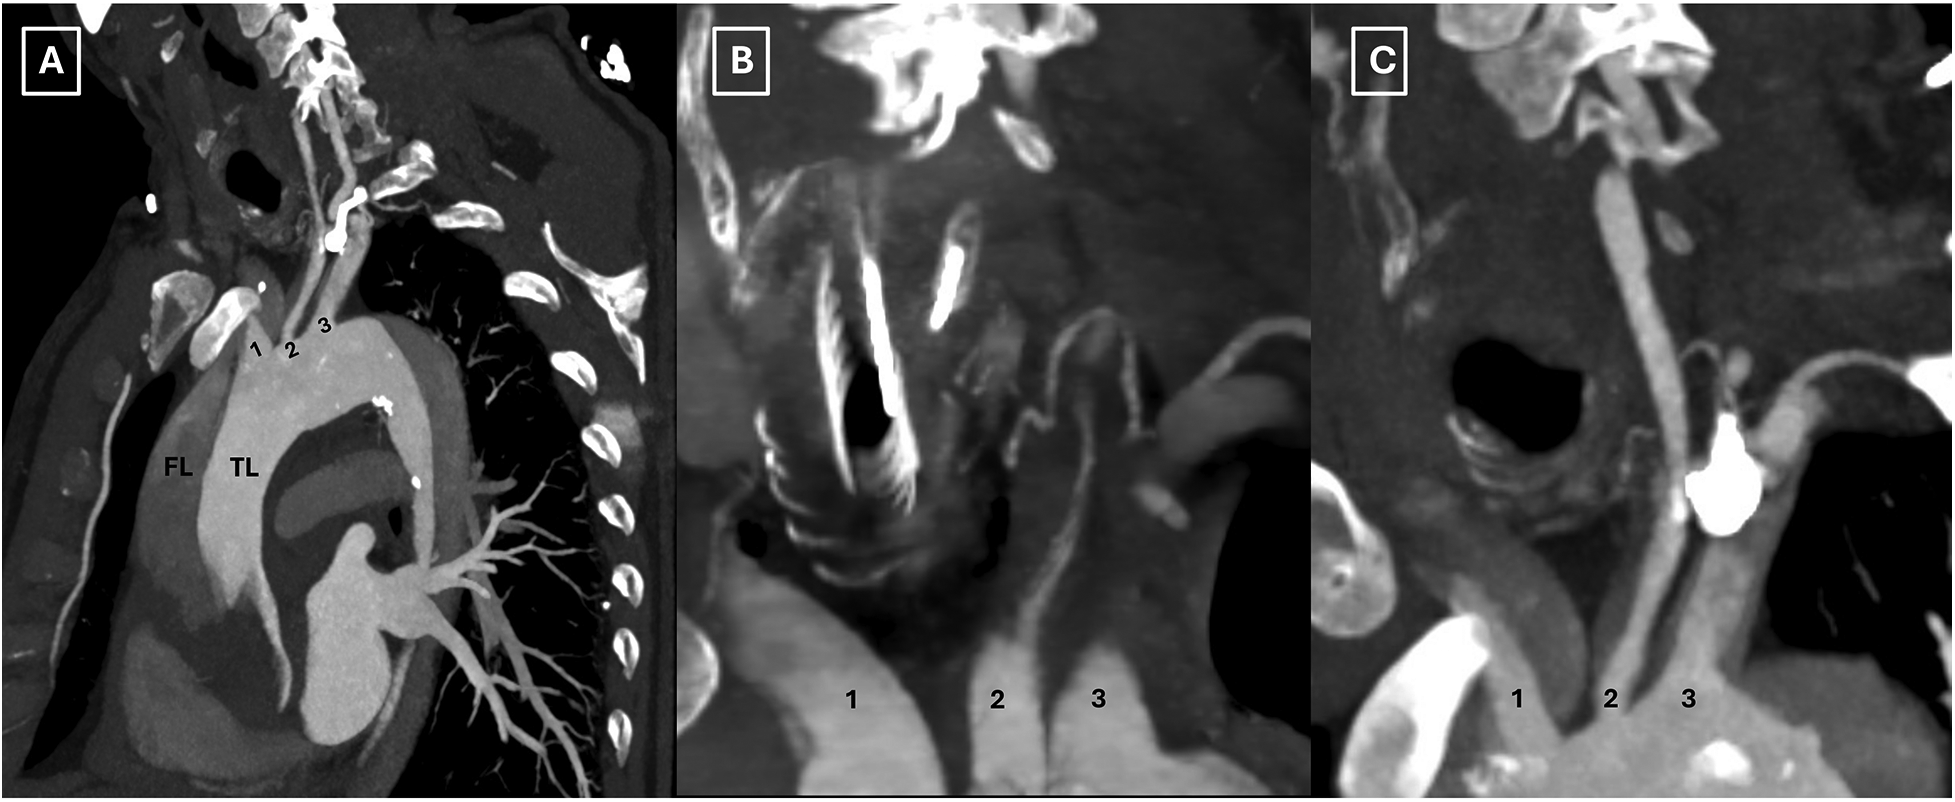

A 63-year-old male, with a history of hypertension, presented to the emergency department with acute, severe, and migratory chest pain of a few hours’ duration. On evaluation, the patient was alert with no neurological deficits, and the physical examination was otherwise noncontributory. A computed tomography (CT) angiography disclosed an acute DeBakey type I aortic dissection extending from the aortic root to the external iliac arteries, including supra-aortic branch (SAB) involvement and hemorrhagic pericardial effusion, while visceral arteries remained unremarkable, however with left kidney malperfusion syndrome (Figures 1A–C, 2A–C).

Figure 2

Preoperative computed tomography scan illustrating the involvement of all supra-aortic branches (A–C). TL: true lumen; FL: false lumen; 1: innominate artery; 2: left common carotid artery; 3: left subclavian artery.